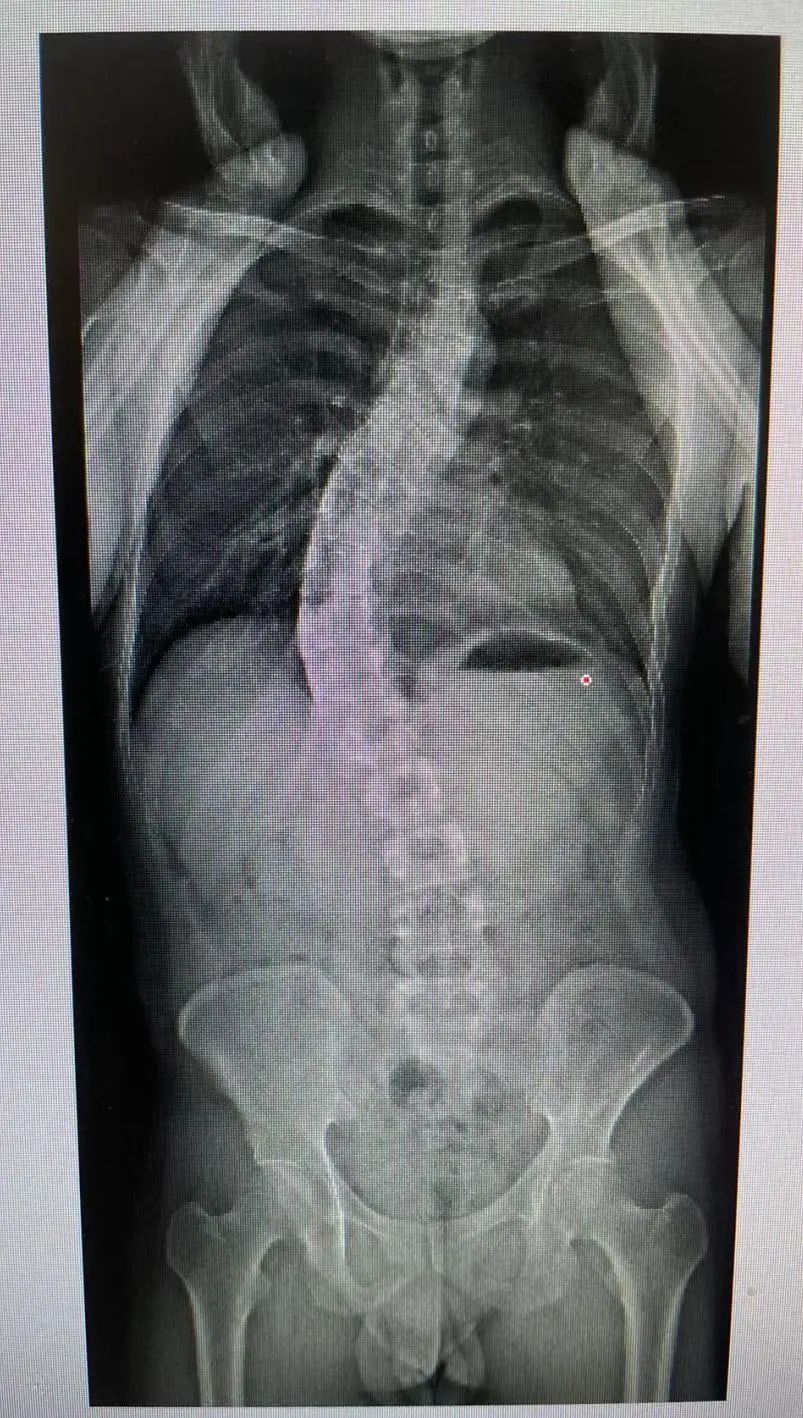

15岁的王同学,两年前家长偶然发现他有点高低肩、含胸驼背,但因学业重,家长也没重视,一直没有治疗,今年暑假来同仁医院骨科就诊,脊柱医生发现他体态不好,做了一个EOS(全身影像系统)全面的检查,显示为严重的脊柱侧弯,家长和孩子都很后悔。

普通的X光片或者CT检查辐射剂量大、检查时间长,而且脊柱侧弯的诊断随访还需要多次拍片,家长总会担心辐射问题。

EOS系统是青少年脊柱侧弯筛查的“白金”解决方案:

一次成像,辐射小,比X片辐射剂量减少约50%,比传统CT扫描减少约95%。

是目前世界上唯一能在受检者负重位(站姿或坐姿)情况下进行全身三维扫描的超低放射剂量的X射线扫描系统。

EOS具有绿色、高效、精准、智能四大优势

EOS总检查时间为4分钟,包括正侧位扫描,极大提高了医院的工作效率。可以精准的重现全身骨骼整体三维结构自动计算临床参数,帮助医生理解和评估脊柱在功能位的平衡与代偿状态。让临床医生能够更直观、更准确、更个性化的为患儿制定诊疗计划。

我院脊柱外科是全国青少年脊柱健康联合研究中心与临床基地,在脊柱侧弯筛查、治疗及手术有着丰富的临床经验。2021年引进了EOS全身骨骼三维建模成像系统,成为上海为数不多拥有这项技术的医院之一,EOS已成为脊柱医生和很多患儿家长的首选。